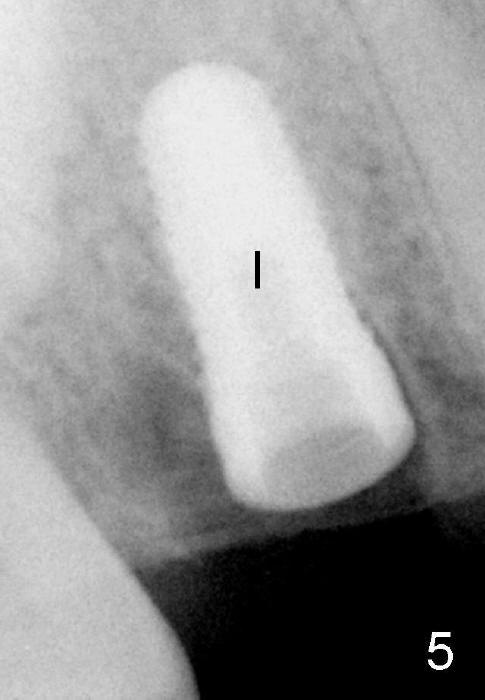

Fig.5: The mesial socket is almost obliterated when a 5.3x12 mm implant (I) is inserted.